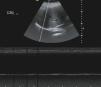

Se inició ventilación no invasiva con BiPAP Vision®, modalidad S/T, con los siguientes parámetros: IPAP 16cm H20; EPAP 6cm H20; FiO2 0,25, mejorando en las primeras 12h de uso la clínica y la gasometría; pH 7,38; pCO2 47mmHg; pO2 82mmHg; bicarbonato 32mEq/l. Ante estos hallazgos, junto con la incapacidad para reducir el número de horas de uso y de volver a los parámetros ventilatorios previos al ingreso, se llevó a cabo un estudio de la motilidad diafragmática e integridad del nervio frénico. El diagnóstico se confirmó, como en la paciente anterior, con el electromiograma y la visualización en la ecografía en modo-M de una ausencia de movimientos diafragmáticos (fig. 2). Una vez superada la fase aguda se demostró mediante espirometría una variación del FVC>20% en decúbito frente a la posición de sedestación y se iniciaron medidas fisioterapéuticas y estudios adicionales.